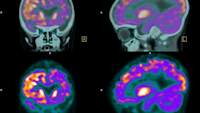

- Fludoxyglucose正电子发射断层扫描(FDG PET)帮助医生了解你的大脑是如何工作的。一种含糖的放射性示踪剂通过静脉注射到你的静脉中,然后医生测量你的大脑代谢葡萄糖的方式(它需要能量)。不同类型的痴呆症在大脑的不同部位有不同的活动模式(通常较低)。例如,在阿尔茨海默氏症中,大脑的中间部分(颞叶和顶叶)的活动较低,而不是前面或后面(像其他类型的痴呆症)。这些测试对已经患有痴呆症的人很有好处,医疗保险和其他类型的健康保险通常会涵盖它。

- 淀粉PET扫描使用粘附在淀粉样斑块的放射性示踪剂,因此它们会出现在扫描上。提供商通常将在70岁的患者上使用淀粉样蛋白宠物扫描,谁具有内存损失,以确定它们是否具有Alzheimer或其他东西,因为扫描可以早期检测变化。但即使他们是FDA批准,除非您是临床试验或研究的一部分,否则没有保险(甚至没有Medicare)将为他们支付。因此,预计距离左右3000美元左右。

- TAU PET扫描只用于研究,也没有对大多数医生提供的,即使他们已被FDA批准。这些测试使用附着到Tau缠结的放射性示踪剂。